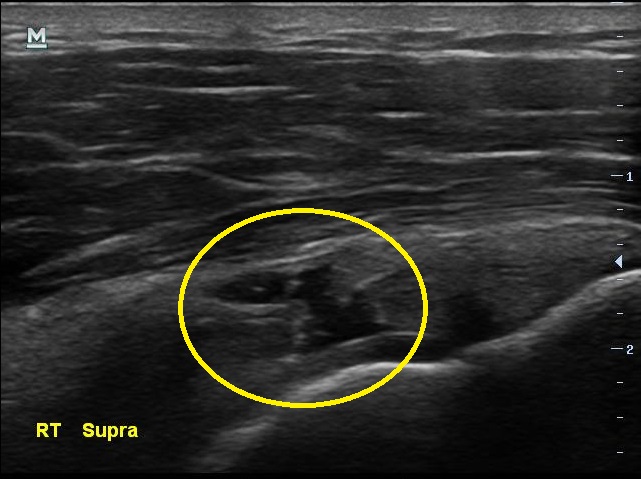

3개월만에 통증이 더 심해졌다고 찾아온 남자분, 검사 결과는 3개월전보다 더 악화 되었습니다.

초음파 검사 결과 3개월전에 비해 극상근 힘줄의 파열 정도가 더 심해져있습니다.